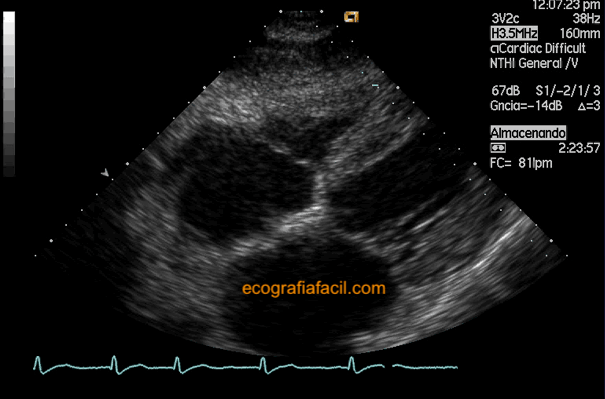

La primera imagen que vamos a obtener será un cuatro cámaras (figura 29) así que el análisis de la contracción, el tamaño de las cavidades y el grosor del miocardio es similar al apical 4 cámaras. Si angulamos un poco más, incluso podremos desplegar la aorta en el centro del corazón y tenemos un 5 cámaras donde podemos poner también un Doppler espectral para hacer mediciones de gradientes. También es posible valorar el llenado mitral, y girando adecuadamente la sonda, obtener una buena alineación de la barra de muestra Doppler continuo con una insuficiencia mitral para, posteriormente, calcular la Presión Sistólica Pulmonar (PSAP) (figura 30).

The first image that we will obtain will be a four chambers (figure 29) so the analysis of the contraction, the size of the cavities and the thickness of the myocardium is similar to the apical 4 chambers. If we angulate a little more, we can even deploy the aorta in the center of the heart and we have a 5 chambers view where we can also put a spectral Doppler to make measurements of gradients. It is also possible to assess mitral filling, and by appropriately rotating the probe, obtain a good alignment of the continuous Doppler sample bar with mitral insufficiency to subsequently calculate the Pulmonary Systolic Pressure (PSAP) (Figure 30).